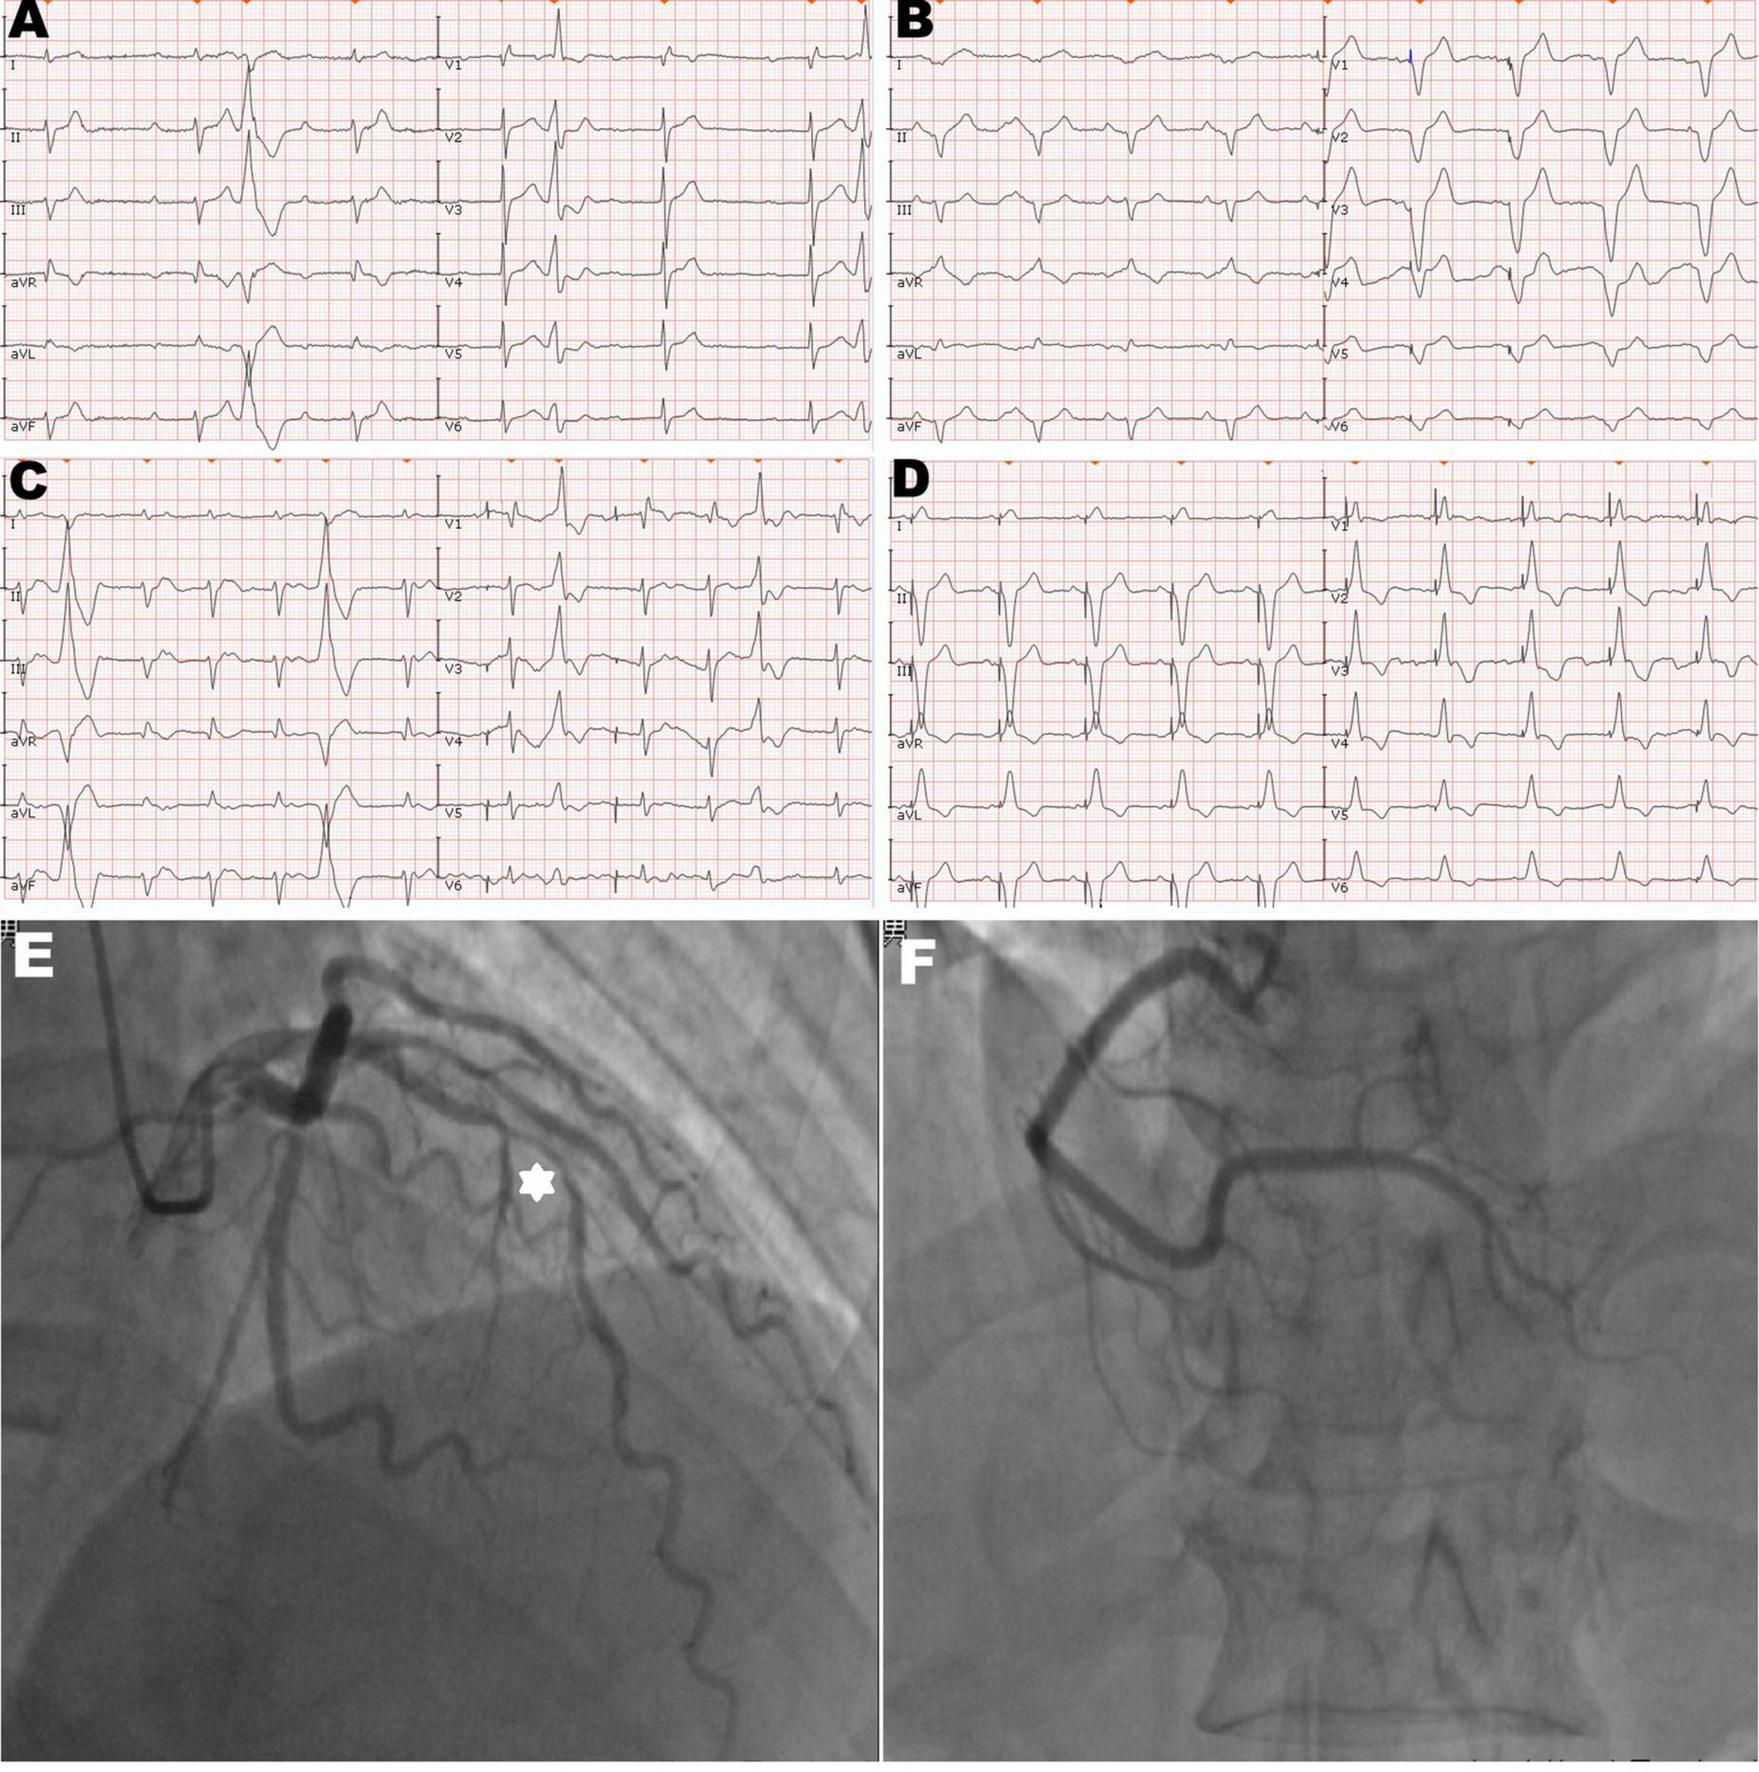

FIGURE 1

Twelve-lead electrocardiogram and coronary angiogram of the patient. (A) The initial electrocardiogram on the admission day showed complete atrioventricular block with frequent premature ventricular contractions. (B) The electrocardiogram immediately after pacemaker (PM) implantation showed the left bundle branch block pattern and the pacing model was VAT. (C) The electrocardiogram on the second post-operative day (POD) showed ventricular pacing failure. (D) The electrocardiogram after transvenous lead extraction and re-fixation showed the right bundle branch block and left axis deviation, and the right ventricular (RV) lead was refixed at the lower RV septum. (E) Hexagonal star symbol shows a diffuse atherosclerotic stenosis was observed in the middle segment of the left anterior descending branch, thus leading to insufficient coronary blood supply on the mid-portion of the interventricular septum. (F) Right coronary artery was relatively normal.

A 92-year-old man was referred to our center for syncope due to a complete atrioventricular block (Figure 1A). His medical history includes coronary atherosclerotic heart disease and chronic obstructive pulmonary disease. Coronary angiography was performed on account of effort angina 3 years ago (Figures 1E, F). Prior coronary angiography revealed a diffuse lesion (percent diameter stenosis 70–80%) in the middle segment of the left anterior descending (LAD) branch (Figure 1E). However, he refused to receive revascularization or medication treatment. During hospitalization, he had no finding of heart failure, and the transthoracic echocardiography (TTE) revealed minor mitral insufficiency and normal LV contraction (ejection fraction: 55%).

We performed dual-chamber PM (HeartTone LD300D, LifeTech Scientific Corporation, Shenzhen, China) implanted via the left subclavian vein on the next day after admission. The implantation procedure can be summarized as follows: under local anesthesia, after a successful puncture of the left subclavian vein, the patient was implanted with a common sheath. Although a superior vena cava stenosis might exist, we did not replace the common sheath with a long sheath. Thus, the manipulation of active fixation leads was very difficult; we attempted to fix RV lead at the RV septum, but it was not as successful. Finally, two active fixation leads were, respectively, placed at the RV apex (SureScan 5076; 58 cm, Medtronic, Minneapolis, MN, USA) and the right atrial appendage (SureScan 5076; 52 cm, Medtronic, Minneapolis, MN, USA) with excellent pacing parameters (intraoperative RV lead impedance and threshold were 1,300 Ω and 1.4 V, respectively). There were no abnormalities or complications during the implantation procedure. X-ray fluoroscopy image immediately after implantation showed that the RV lead was fixed properly (Figure 2A). Electrocardiogram immediately after implantation showed the left bundle branch block pattern (Figure 1B).

However, on the second postoperative day (POD), the patient complained of unrelenting chest pain and syncope. A subsequent immediate chest X-ray identified that the RV lead tip migrated to the region outside the left cardiac margin (Figure 2B). A thoracic computed tomography (CT) scan revealed that the RV lead passed through the interventricular septum and the left LV free wall, and finally reached the left of the pericardial cavity. Furthermore, as the thoracic CT scan also showed a small amount of left pleural effusion (Figure 2B) and there were no obvious symptoms of pericardial tamponade (Figures 2C, D), we deduced that the lead had already penetrated the pericardium. Electrocardiogram and interrogation showed loss of ventricular capture (Figure 1C).

The subsequent patient’s management was thoroughly debated. Patients may not tolerate surgical lead extraction due to the variety of severe chronic diseases and advanced age. Therefore, on the 5th POD, we performed transvenous lead extraction under transesophageal echocardiography monitored and cardiac surgery backup. Figures 3A–D depict and describe the entire procedure in detail. Transvenous lead extraction was uncomplicated and did not have any hemodynamic instability, and intraoperative ultrasonography monitoring showed no increase in pleural effusion and pericardial effusion. The original RV lead was refixed at the lower RV septum to reduce the risk of perforation and consequent tamponade. Subsequent electrocardiogram and PM interrogation revealed the PM functioning normally with excellent pacing parameters (intraoperative RV lead impedance and threshold were 1,020 Ω and 1.0 V, respectively) (Figure 1D). On the 10th POD, the patient was discharged, and the subsequent 6 months of follow-up were uneventful.